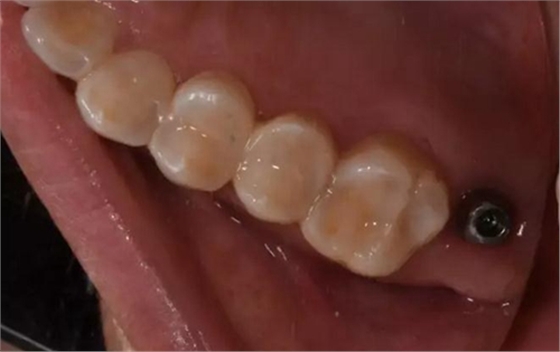

術后口內照片

修復體戴入口內后照片,與鄰牙鄰接良好。